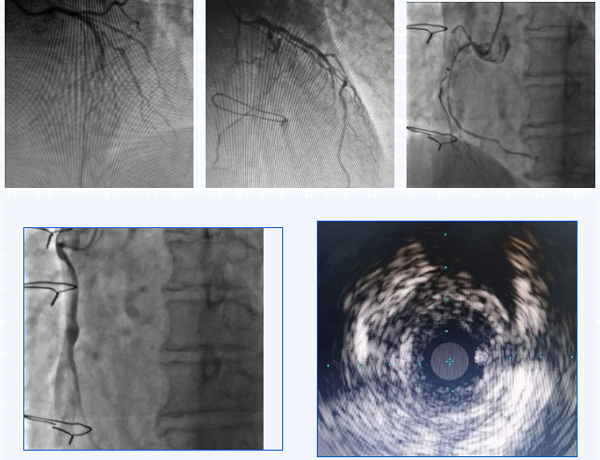

75岁的李先生在20年前行冠状动脉搭桥手术,撘了3根桥。近2年反复胸闷胸痛发作,最近3月症状加重,快走或上楼后就会出现明显的胸痛伴背痛,就诊于我院心内科。行冠状动脉造影检查,可以看到冠状动脉原有的三根血管前降支,回旋支,右冠状动脉均有弥漫性的狭窄阻塞:右冠状动脉远端闭塞,前降支的乳内动脉桥,回旋支的大隐静脉桥血管通畅,但右冠状动脉桥血管远端吻合口闭塞且伴有血栓形成,可见右冠桥血管内明显的造影剂滞留。

经过充分的准备,在心内科主任刘巍教授的指导下,介入经验丰富的术者心内科主范军任医师和助手兰永昊医生对静脉桥血管进行介入治疗。考虑桥血管病变的特殊性,尤其是静脉桥血管,盲目扩张很容易导致更严重的并发症出现。仅从造影来看,无法完全明确桥血管内病变性质特点,在导丝通过闭塞血管段后,使用血管内超声进行检查可见到,桥血管远端吻合口部位为纤维组织增生为主,桥血管内无明显血栓。然而球囊扩张吻合口时由于病变坚硬,多次出现球囊滑脱难以扩张成功,刘巍与范军根据病变特点,决定在准分子激光对桥血管进行充分消蚀的基础上,再次扩张血管。激光消蚀后,血流明显改善,狭窄程度也有减轻,之后再次使用球囊扩张可见扩张效果非常满意,基本无残余狭窄,植入药物球囊,未植入支架,最终效果非常满意。